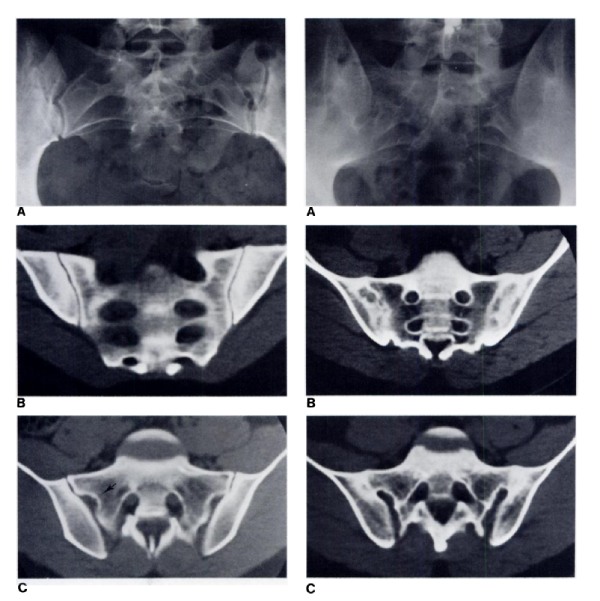

Chụp CT cho thấy hình ảnh bất thường, các mức độ tổn thương khác nhau của khớp cùng chậu. Phương pháp này cũng có thể cho thấy tình trạng khe khớp cùng chậu rộng, xơ cứng trên bề mặt khớp, bào mòn khớp, dính một phần hoặc hoàn toàn khớp cùng chậu,… Dựa vào kết quả, bác sĩ sẽ chẩn đoán tình trạng viêm của khớp cùng chậu ở giai đoạn trung bình hoặc nghiêm trọng.

Kết quả chụp cộng hưởng từ cho thấy mức độ tổn thương của khớp cùng chậu, cơ, dây chằng, vết nứt gãy nhỏ tại khớp. Với phương pháp này, bác sĩ có thể chẩn đoán mức độ viêm của khớp cùng chậu từ giai đoạn khởi phát mà chụp X Quang và CT không phát hiện được.